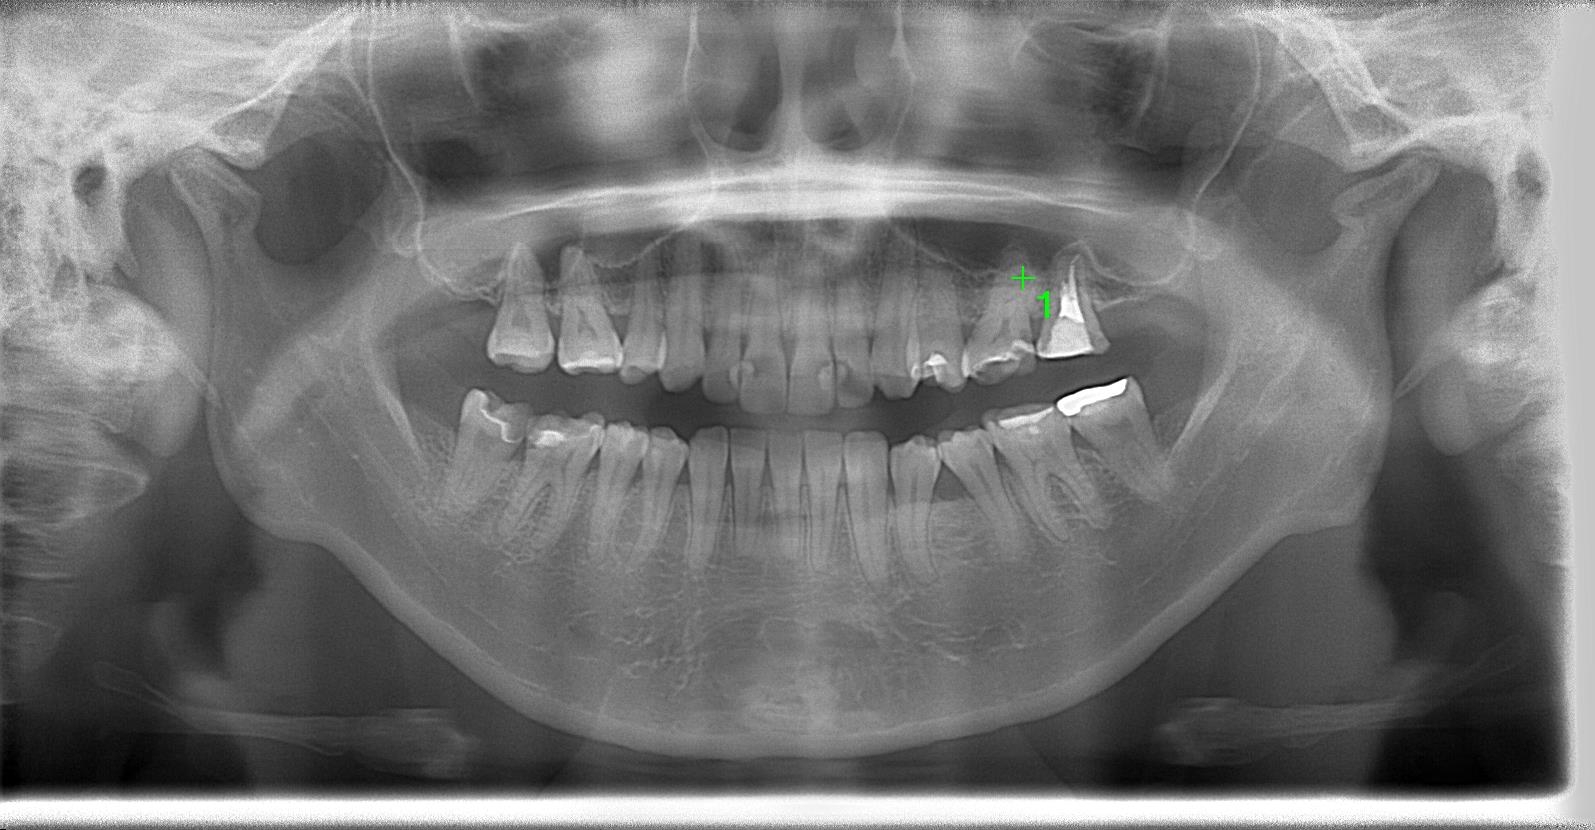

パノラマレントゲン写真